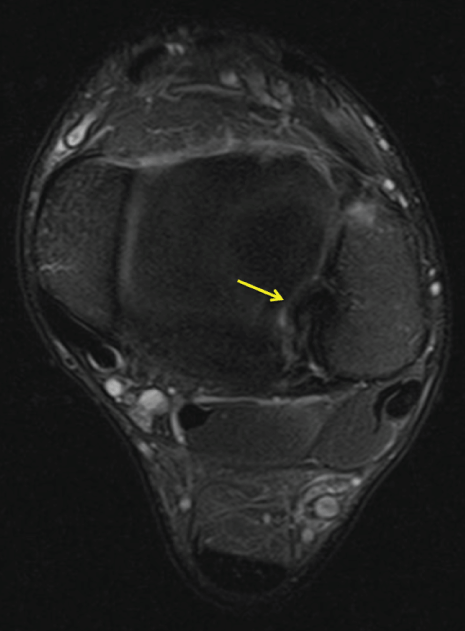

Thirteen year old boy with no medical history consulted our medical department for the spontaneous appearance of a progressively growing though painless mass on the medial aspect of his right knee. Intake excluded any kind of clinical or functional symptomatology or preceding traumatic events. Physical examination revealed a soft, painless, mobile, mass on the medial side of the knee joint. Strength and range of motion were preserved, painless medial joint interline palpation and negative medial meniscus manoeuvres. The ultrasound exam documented a cystic mass, apparently emerging from the bursa anserine (Figure 5). Additionally, 13 cubic centimetres of blood-synovial fluid were obtained when a puncture was performed. MRI demonstrated a bilobed collection that was located between the tendons of the pes anserinus and the tibial plateau (Figure 6 and Figure 7). As a focal extra-articular PVNS was suspected, the patient was referred to a hospital where an open bursectomy and pathological examination were performed. The result of microscopic and macroscopic exams confirmed the diagnosis of PVNS. No postoperative complications were reported and the patient remained asymptomatic.

Figure 7: Axial MRI image showing hemosiderin deposition (arrows) were observed in an extra-articular location, the bursa anserine.

View Figure 7